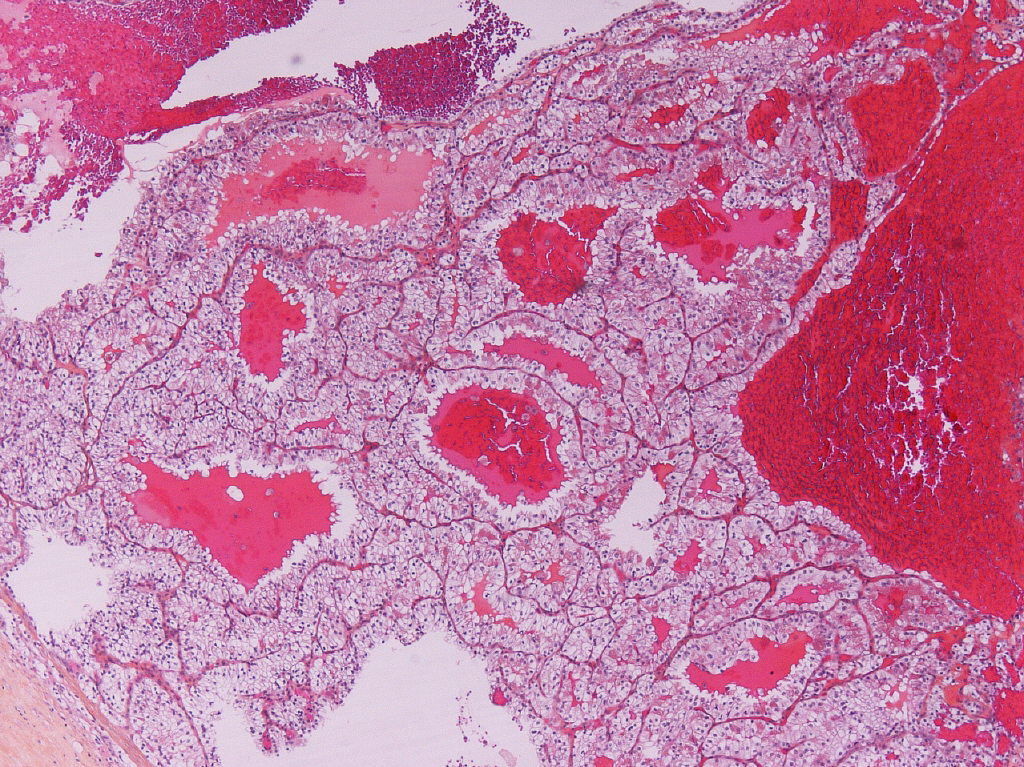

Classification of renal tumors